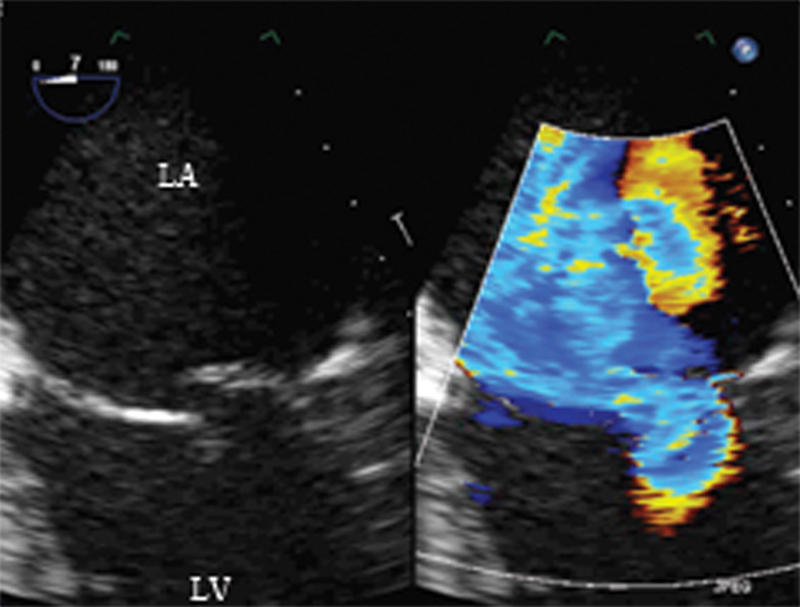

فحوصات تشخيصية لبعض امراض القلب والشرايين التاجية